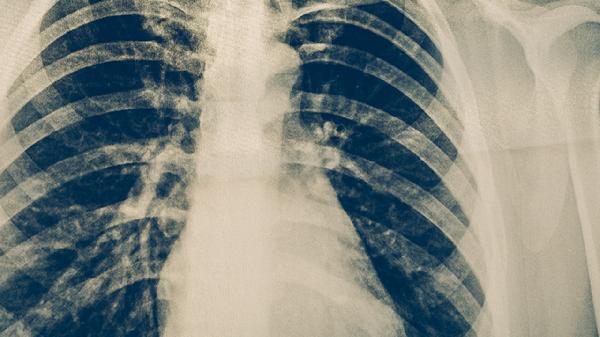

肺结核的治疗是一个长期、规范的过程,患者必须严格遵循医嘱,完成足量、足疗程的联合化疗,切忌自行停药或更改剂量,否则极易导致治疗失败或产生耐药。在药物治疗期间,应保证充足的营养支持,多摄入富含优质蛋白和维生素的食物,如鸡蛋、牛奶、瘦肉、新鲜蔬菜水果等,以增强机体修复能力。保持居住环境通风,注意休息,避免劳累和情绪波动,进行适度的康复锻炼。定期复查胸部影像学和痰菌检查至关重要,以便医生评估疗效和调整方案。若出现恶心、皮疹、黄疸、视力异常等不适,应及时与医生沟通。